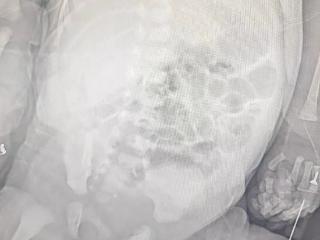

罕见!新生儿自发性脾破裂出血,青岛市妇女儿童医院新生儿外科团队争分夺秒止血保脾